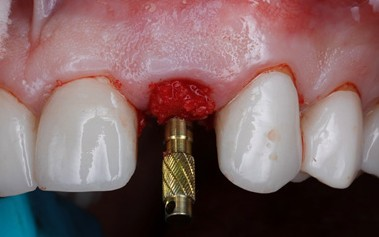

Once both temporary abutments were passively seated, the temporary shells were adjusted to be seated over the abutments freely. Sometimes some adjustment can be needed to increase the diameter of the abutment hole.

The custom shells were picked up using a self-cure composite based temporary material (Integrity), the wings can be removed at this stage and the “sub- critical zone” of the emergence profile was customized chairside by hand using a flowable composite and football diamond bur